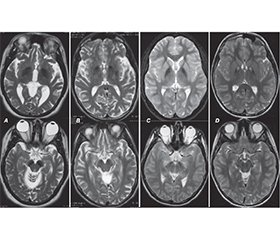

Нейродегенерації з накопиченням заліза в головному мозку (ННЗМ) становлять групу генетично детермінованих і клінічно неоднорідних форм прогресуючої неврологічної патології, пов’язаної з відкладанням заліза в базальних гангліях та інших структурах великого мозку, що, у свою чергу, призводить до порушення їх функції. Захворювання може дебютувати і проявлятися як у дитячому, так і в дорослому віці. Мета роботи: привернути увагу лікарів до важливості своєчасної діагностики нейродегенеративних захворювань, які проявляються порушеннями рухової активності і аномальним накопиченням заліза в різних структурах мозку. У клінічній картині ННЗМ переважають рухові розлади, здебільшого поєднання паркінсонізму, дистонії, пірамідної недостатності й атаксії. Ділянки відкладання заліза виявляються на МРТ як білатеральні гіподенсивні зони, у центрі яких у багатьох випадках визначаються гіперденсивні вогнища, ймовірно, за рахунок гліозу переважно в ділянці блідих куль (симптом «око тигра»). Типові нейровізуалізаційні ознаки дозволяють з високою ймовірністю встановити попередній діагноз ННЗМ за наявності, а іноді й до виникнення клінічних проявів захворювання, скорочуючи час та витрати на додаткові дослідження. У роботі описаний клінічний випадок ННЗМ, асоційованої з білком мітохондріальної мембрани, а також висвітлені новітні дані про клінічні прояви, діагностику та сучасний менеджмент такої патології. Продемонстровано можливість і важливість сучасної діагностики і терапії в дитячому віці. Генетичне обстеження залишається вирішальним для верифікації спадково-дегенеративного захворювання та визначення його форми. Аналіз літературних даних і результати власних спостережень підтверджують важливість наведених основних напрямків доступного симптоматичного лікування, а також підходи до патогенетичної терапії, які ще потребують подальших клінічних випробувань. Наведене клінічне спостереження та проведений аналіз даних літератури з проблеми ННЗМ відображають доцільність пошуку у хворих з руховими (екстрапірамідними, пірамідними, координаторними) розладами характерних нейровізуалізаційних патернів з подальшою верифікацією діагнозу шляхом молекулярно-генетичного дослідження.

Neurodegenerations with brain iron accumulation (NBIA) constitute a group of genetically determined and clinically heterogeneous forms of progressive neurological pathology associated with the accumulation of iron in the basal ganglia and other structures of the brain, which, in turn, causes their dysfunction. Both childhood and adulthood onset of the disease is possible. Objective: to draw the attention of doctors to the importance of timely diagnosis of neurodegenerative diseases, which are manifested by movement disorders and abnormal accumulation of iron in various structures of the brain. Movement disorders, mostly a combination of parkinsonism, dystonia, pyramidal insufficiency and ataxia, are dominant in the clinical picture of NBIA. Areas of iron deposition are detected on magnetic resonance imaging as bilateral hypodense zones, in the center of which hyperdense foci are determined in many cases, probably due to the gliosis, mainly in the area of the globus pallidus (eye-of-the-tiger sign). Typical neuroimaging signs help make a preliminary diagnosis of NBIA with a high probability, in the presence and sometimes even before the appearance of clinical manifestations of the disease, reducing costs and time for additional research. The paper describes a clinical case of NBIA associated with the protein of the mitochondrial membrane, and also highlights the latest data on clinical manifestations, diagnosis and modern management of this pathology. The possibility and importance of modern diagnosis and therapy in childhood have been demonstrated. Genetic examination remains crucial for the verification of the hereditary degenerative disease and determination of its form. The analysis of literature data and the results of own observations confirm the importance of the given main directions of available symptomatic treatment, as well as approaches to pathogenetic therapy, which still require further clinical trials. The given clinical observation and the analysis of literature data on the problem of NBIA reflect the expediency of searching for characteristic neuroimaging patterns in patients with motor (extrapyramidal, pyramidal, coordination) disorders with further verification of the diagnosis by means of molecular genetic research.